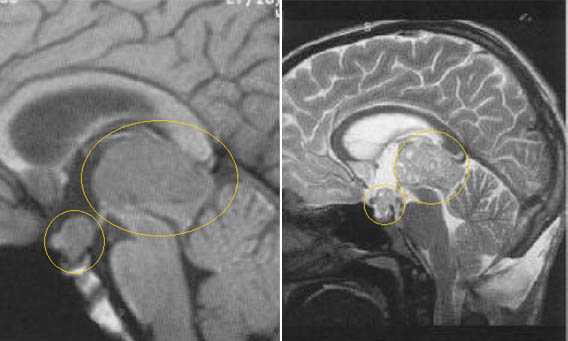

Герминома пинеальной области. На Т2 ВИ опухоль имеет слабо гиперинтенсивный сигнал по сравнению с тканью мозга, тогда как на Т1 опухоль практически изоинтенсивна с мозгом. Желудочковая система гидроцефально расширена. III желудочек деформирован. Четверохолмная пластинка оттеснена кзади.

Герминома пинеальной области. Опухоль имеет гетерогенное строение с множеством мелких и крупных кист. Вокруг опухоли определяется перифокальный отек.

Герминома пинеальной области с метастазированием в хиазмально-селлярную область.

Герминома подкорковых образований слева. Мультикистозного строения опухоль с признаками окклюзии отверстия Монро слева.